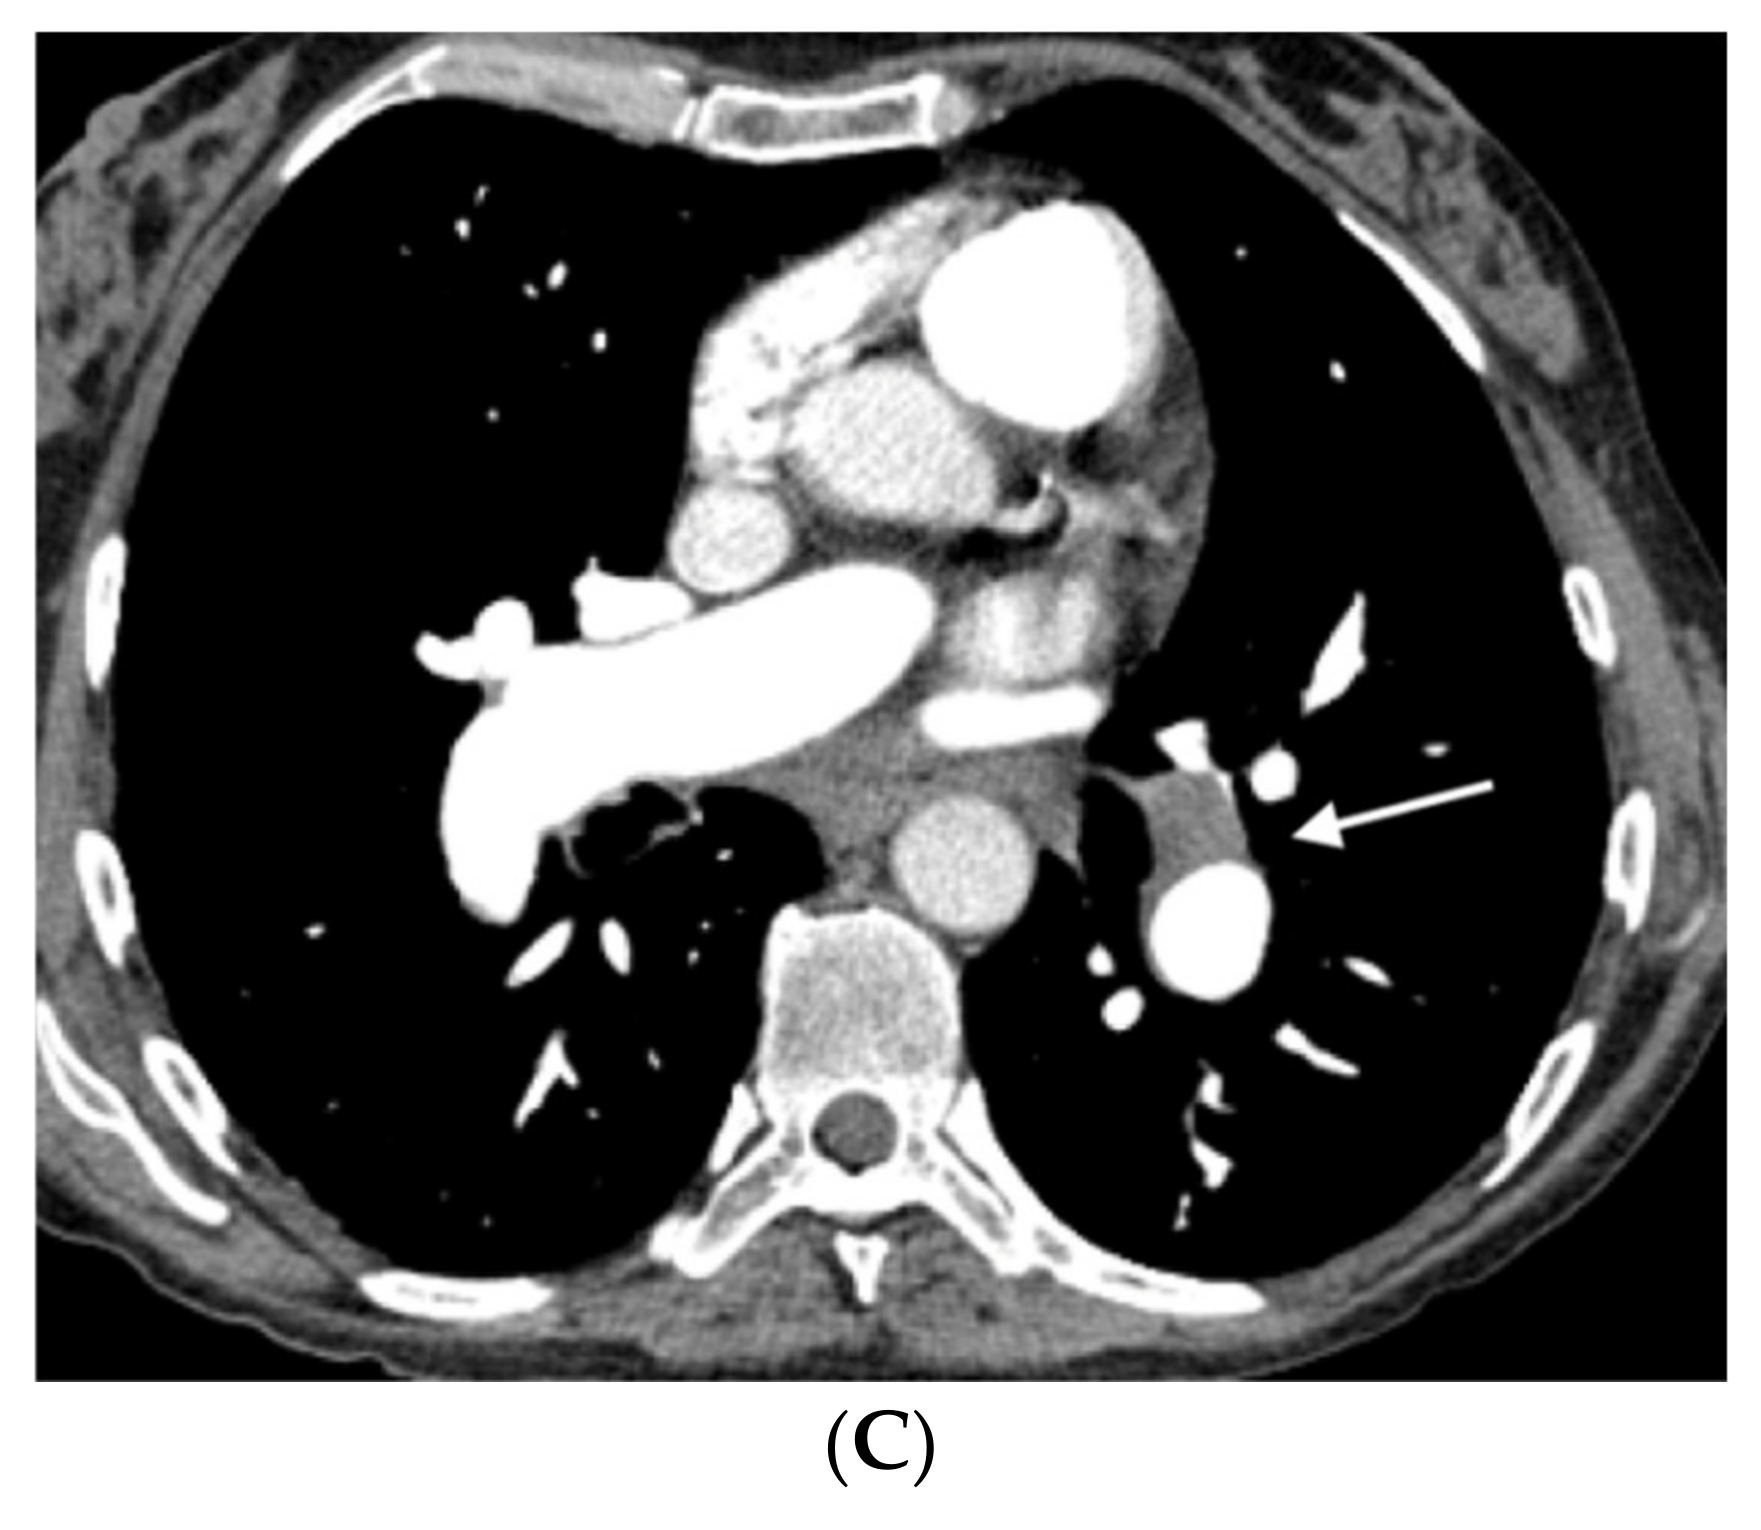

Figure 5.

Forty-seven-year-old woman with sporadic PVOD and three typical findings. (A) Ground glass parenchymal involvement with central geographic distribution (circle) and peripheral centrilobular (curved arrows). Septal lines in basal regions of both lungs (straight arrows); (B) mediastinal lymphadenopathy in the lower right paratracheal location (short arrow) and prevascular (arrow). Right pleural effusion (asterisk).